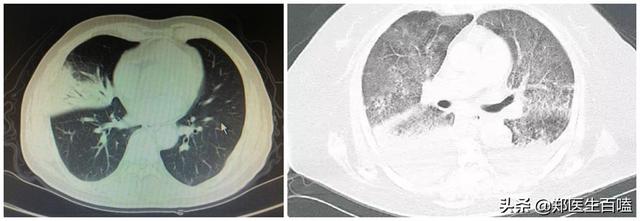

(左が典型的な小葉性肺炎(細菌感染)、右がウイルス性肺炎)